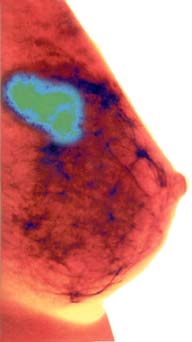

Eficacia de las mamografías

mamograma-byn Las mujeres que se hacen mamogramas regularmente pudieran reducir en 60 por ciento su riesgo de morir de cáncer de mama, según un estudio de la Sociedad Norteamericana del Cáncer. "Las mujeres deberían ser informadas de que si se examinan regularmente reducirán sus riesgos de morir de cáncer mamario por aproximadamente dos tercios", dijo el epidemiologista Robert A. Smith. Siete importantes estudios realizados en EU y Europa han mostrado ya que los mamogramas salvan vidas. El estudio encontró que aquellas mujeres que cumplían con las recomendaciones de exámenes redujeron el riesgo de morir de cáncer por 63 por ciento en relación con los inicios de los setenta, cuando los mamogramas no eran realizados rutinariamente.